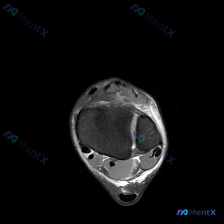

看到一个挺有代表性的读片问题,整理一下完整的分析思路分享给大家。 病例基础信息 这是一份单张踝关节MRI T2序列轴位图像,临床疑问是观察到「软组织积液」,需要解读。 影像结构完整评估 我们先把影像上能看到的结构逐一梳理清楚: 1. 骨骼结构:可见胫腓骨远端截面,骨皮质轮廓清晰,骨髓信号没有异常高信...

最近看到一个挺有讨论价值的读片病例,整理了整个分析思路分享给大家。 病例背景 本次分析对象为踝关节MRI-T2序列-轴位单一扫描层面,患者主诉怀疑存在软组织积液,要求对影像进行评估。 --- 影像核心信息整理 先给大家整理一下这张影像的关键发现: 1. 解剖结构层面:该层面位于踝关节上方,可显示胫骨...